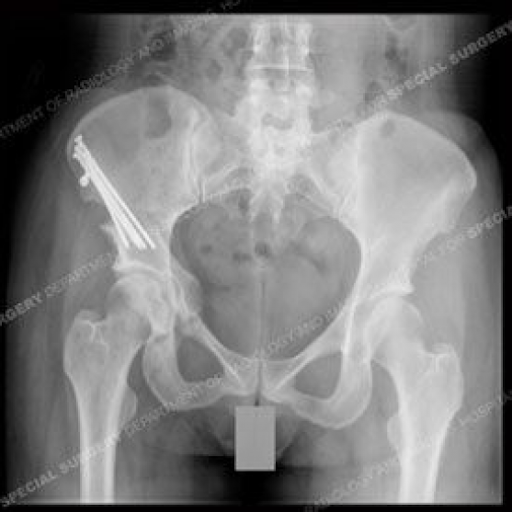

Hip Dysplasia Surgery

In this procedure the surgeon makes an incision in the front of the hip to reach the joint cutting into the pelvic bone to free the hip socket from the pelvis. The goal is to change the orientation of the socket so it can better cover the ball of the hip joint. Hip Dysplasia In Adolescents And Young Adults Hss Hipproblems In 2020 Hip Dysplasia Hip Surgery Hip Displasia Hip dysplasia may occur at birth or develop in early life. Hip dysplasia surgery . Thr involves using plastic and metal implants to replace the entire hip joint bringing hip function back to a more normal range and eliminating most hip dysplasia related discomfort. In a periacetabular per e as uh tab yoo lur osteotomy the socket is cut free from the pelvis and then repositioned so that it matches up better with the ball. Sometimes surgery is needed to fit the joint together properly. The condition can create a gradual misalignment or dislocation of the hip which can wear down cartilage and lead to early onse...